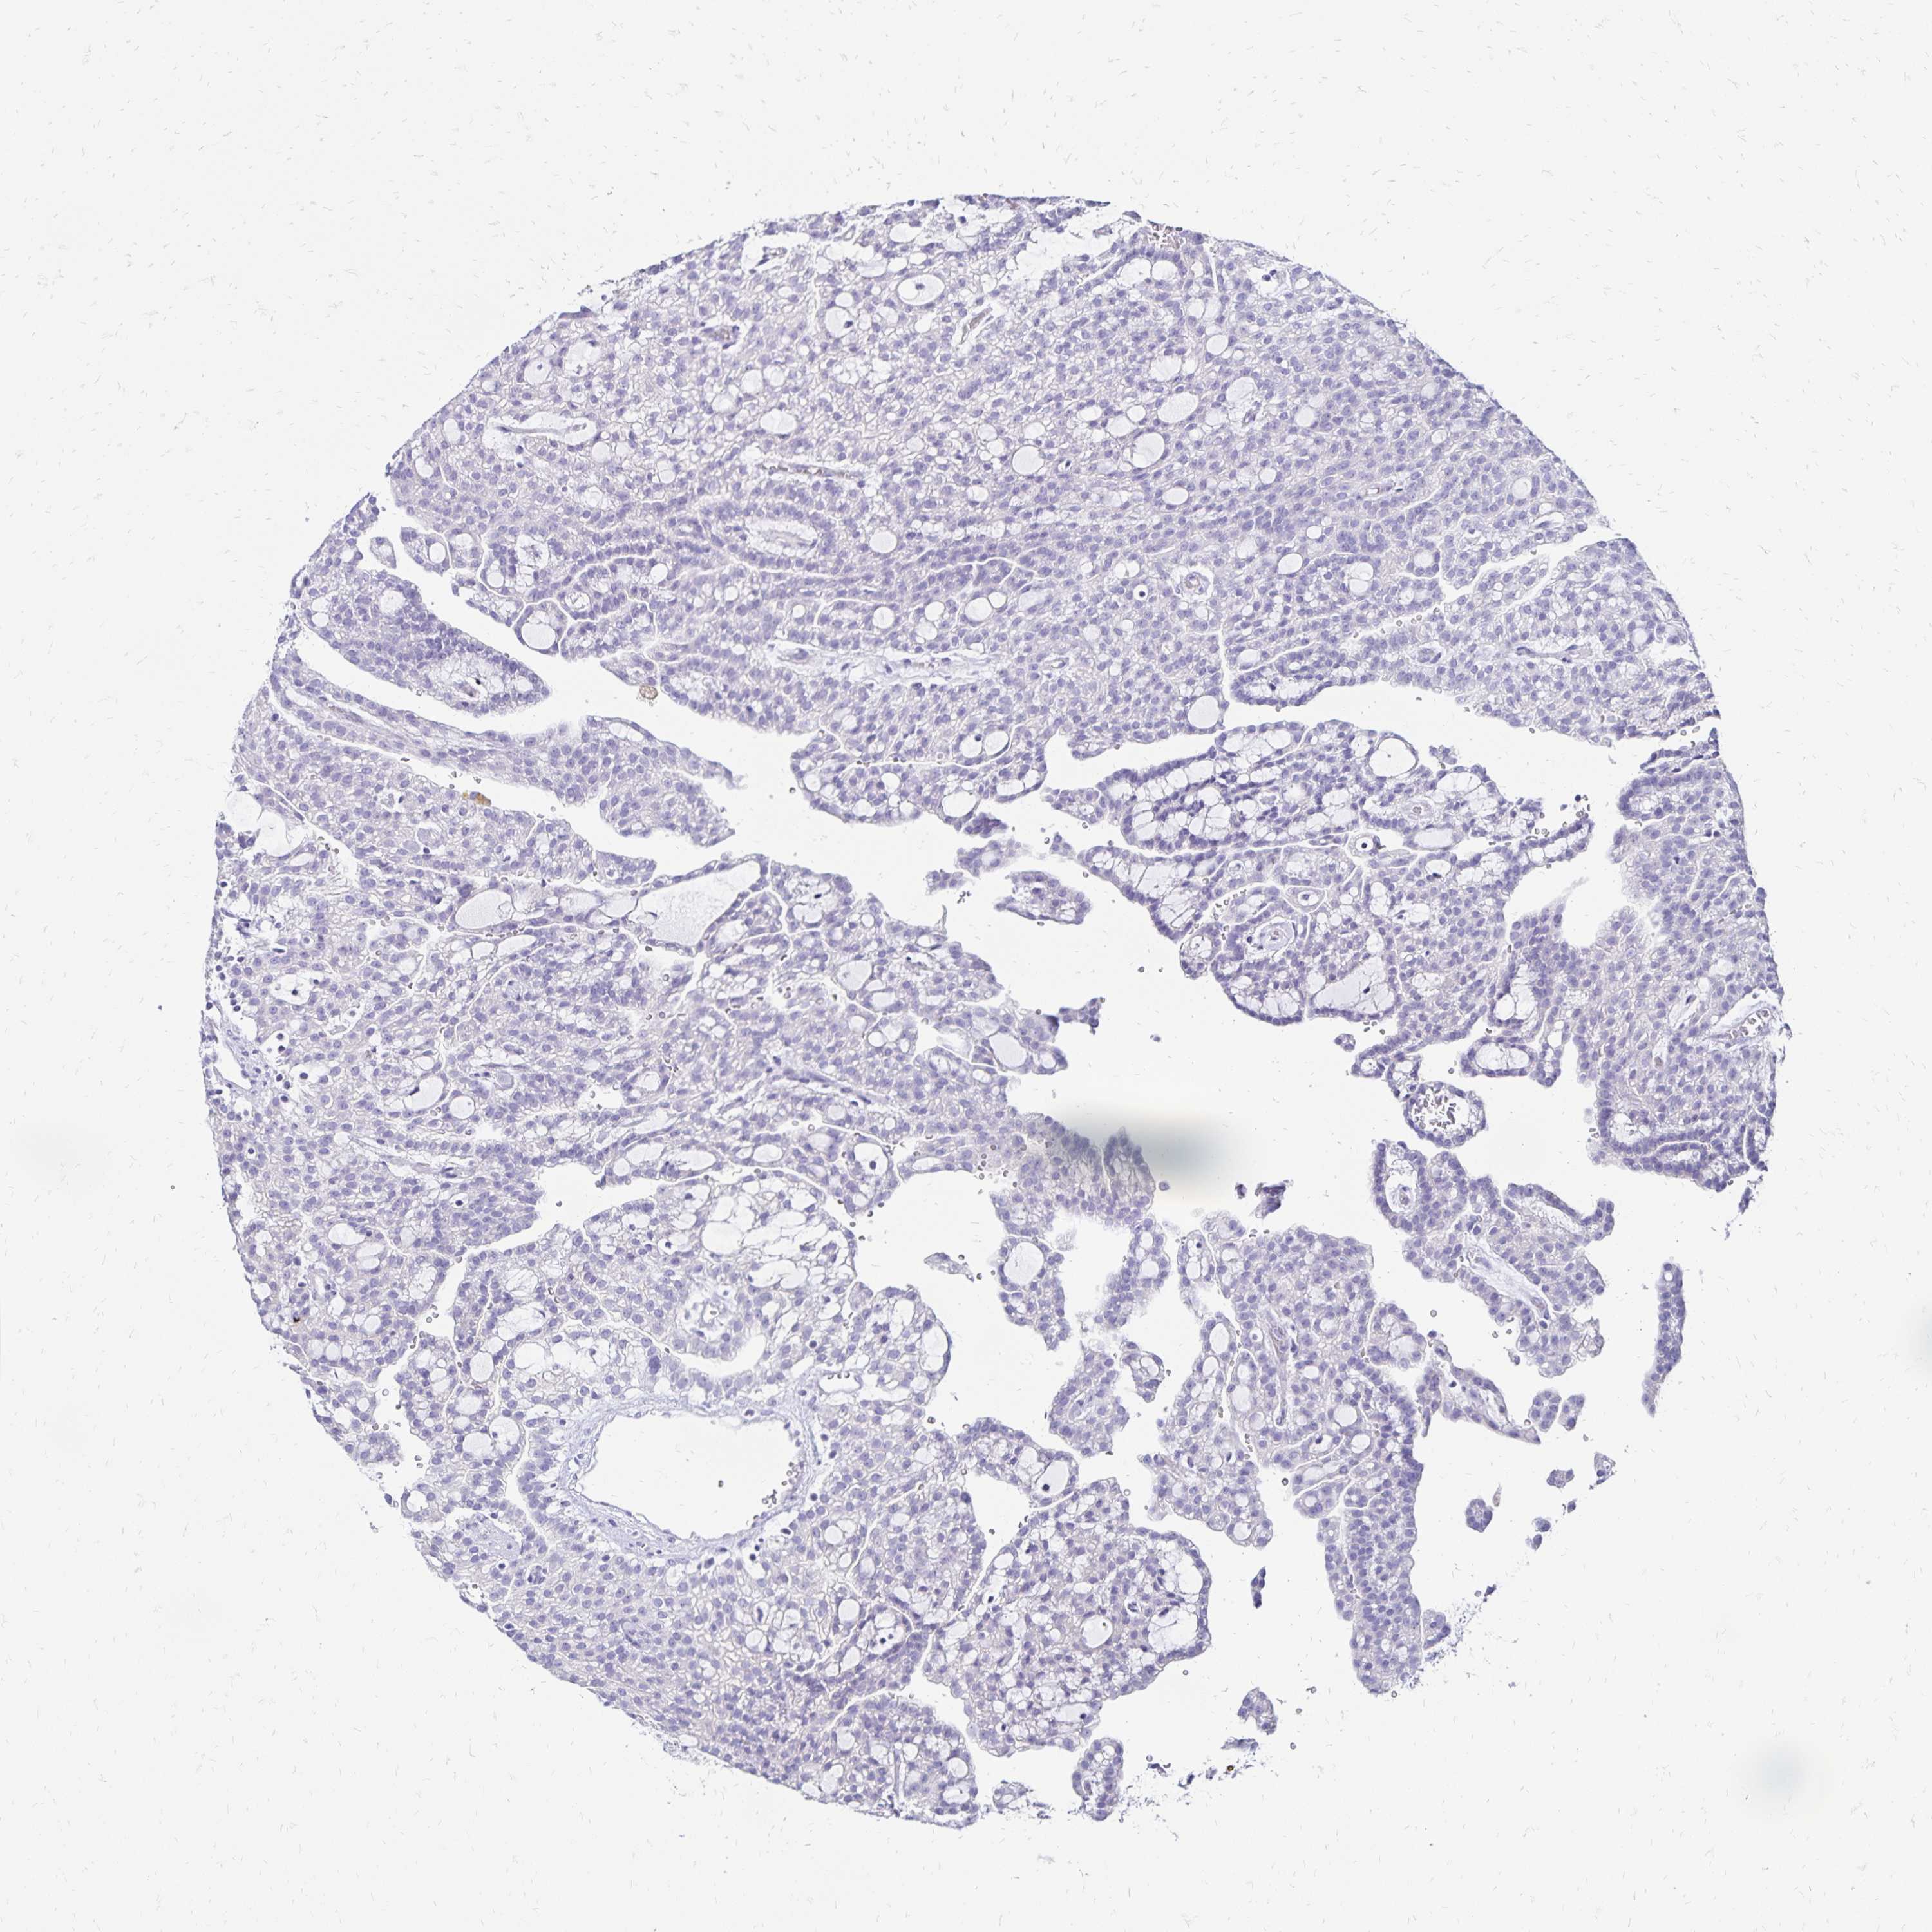

CANCER RENAL CANCER Show tissue menu

KICH TCGA KIRC TCGA KIRC VALIDATION KIRP TCGA PROTEIN RCC CPTAC PROTEIN EXPRESSION

Kidney renal clear cell carcinoma

Kidney renal papillary cell carcinoma